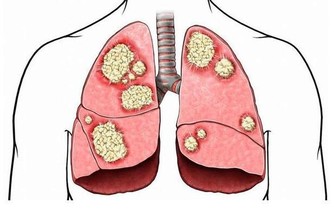

長期睡不好會增加糖尿病發生的風險,加重血糖波動

有研究人員對一家大公司的男性職工進行長期的跟踪調查,

結果發現其中有4800人患有睡眠障礙症,

4年後,他們患高血壓的比例比正常人高兩倍,

8年後,他們患糖尿病的人數增加了三倍。

由此可見,睡眠不好的人患糖尿病風險比正常人更高。